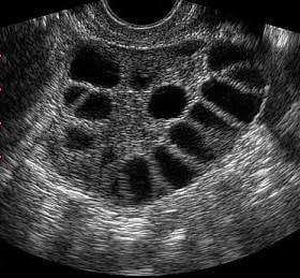

Diagnose the condition.

Hints-Showing USG of Ovary of an unmarried women of reproductive age group.She has a history of dysmenorrhoea with acne on face and hirsutism.

Polycystic ovarian syndrome